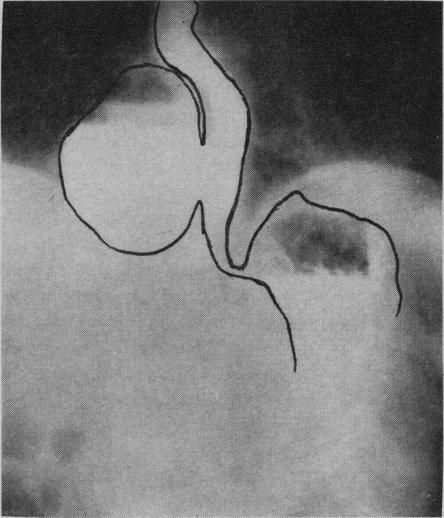

Diverticula of the oesophagus.

Can Med Assoc J. 1957 May 15;76(10):822-31.